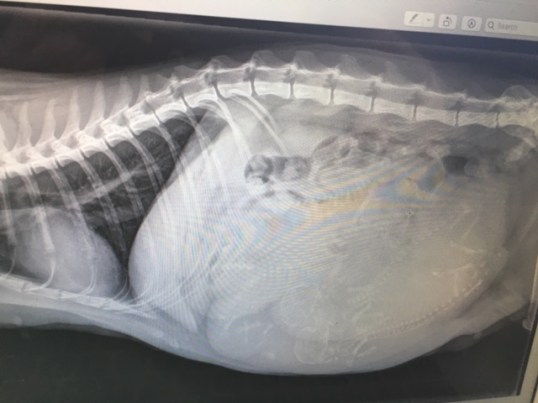

And yes, Baby Girl was VERY pregnant. How many kittens do you see??